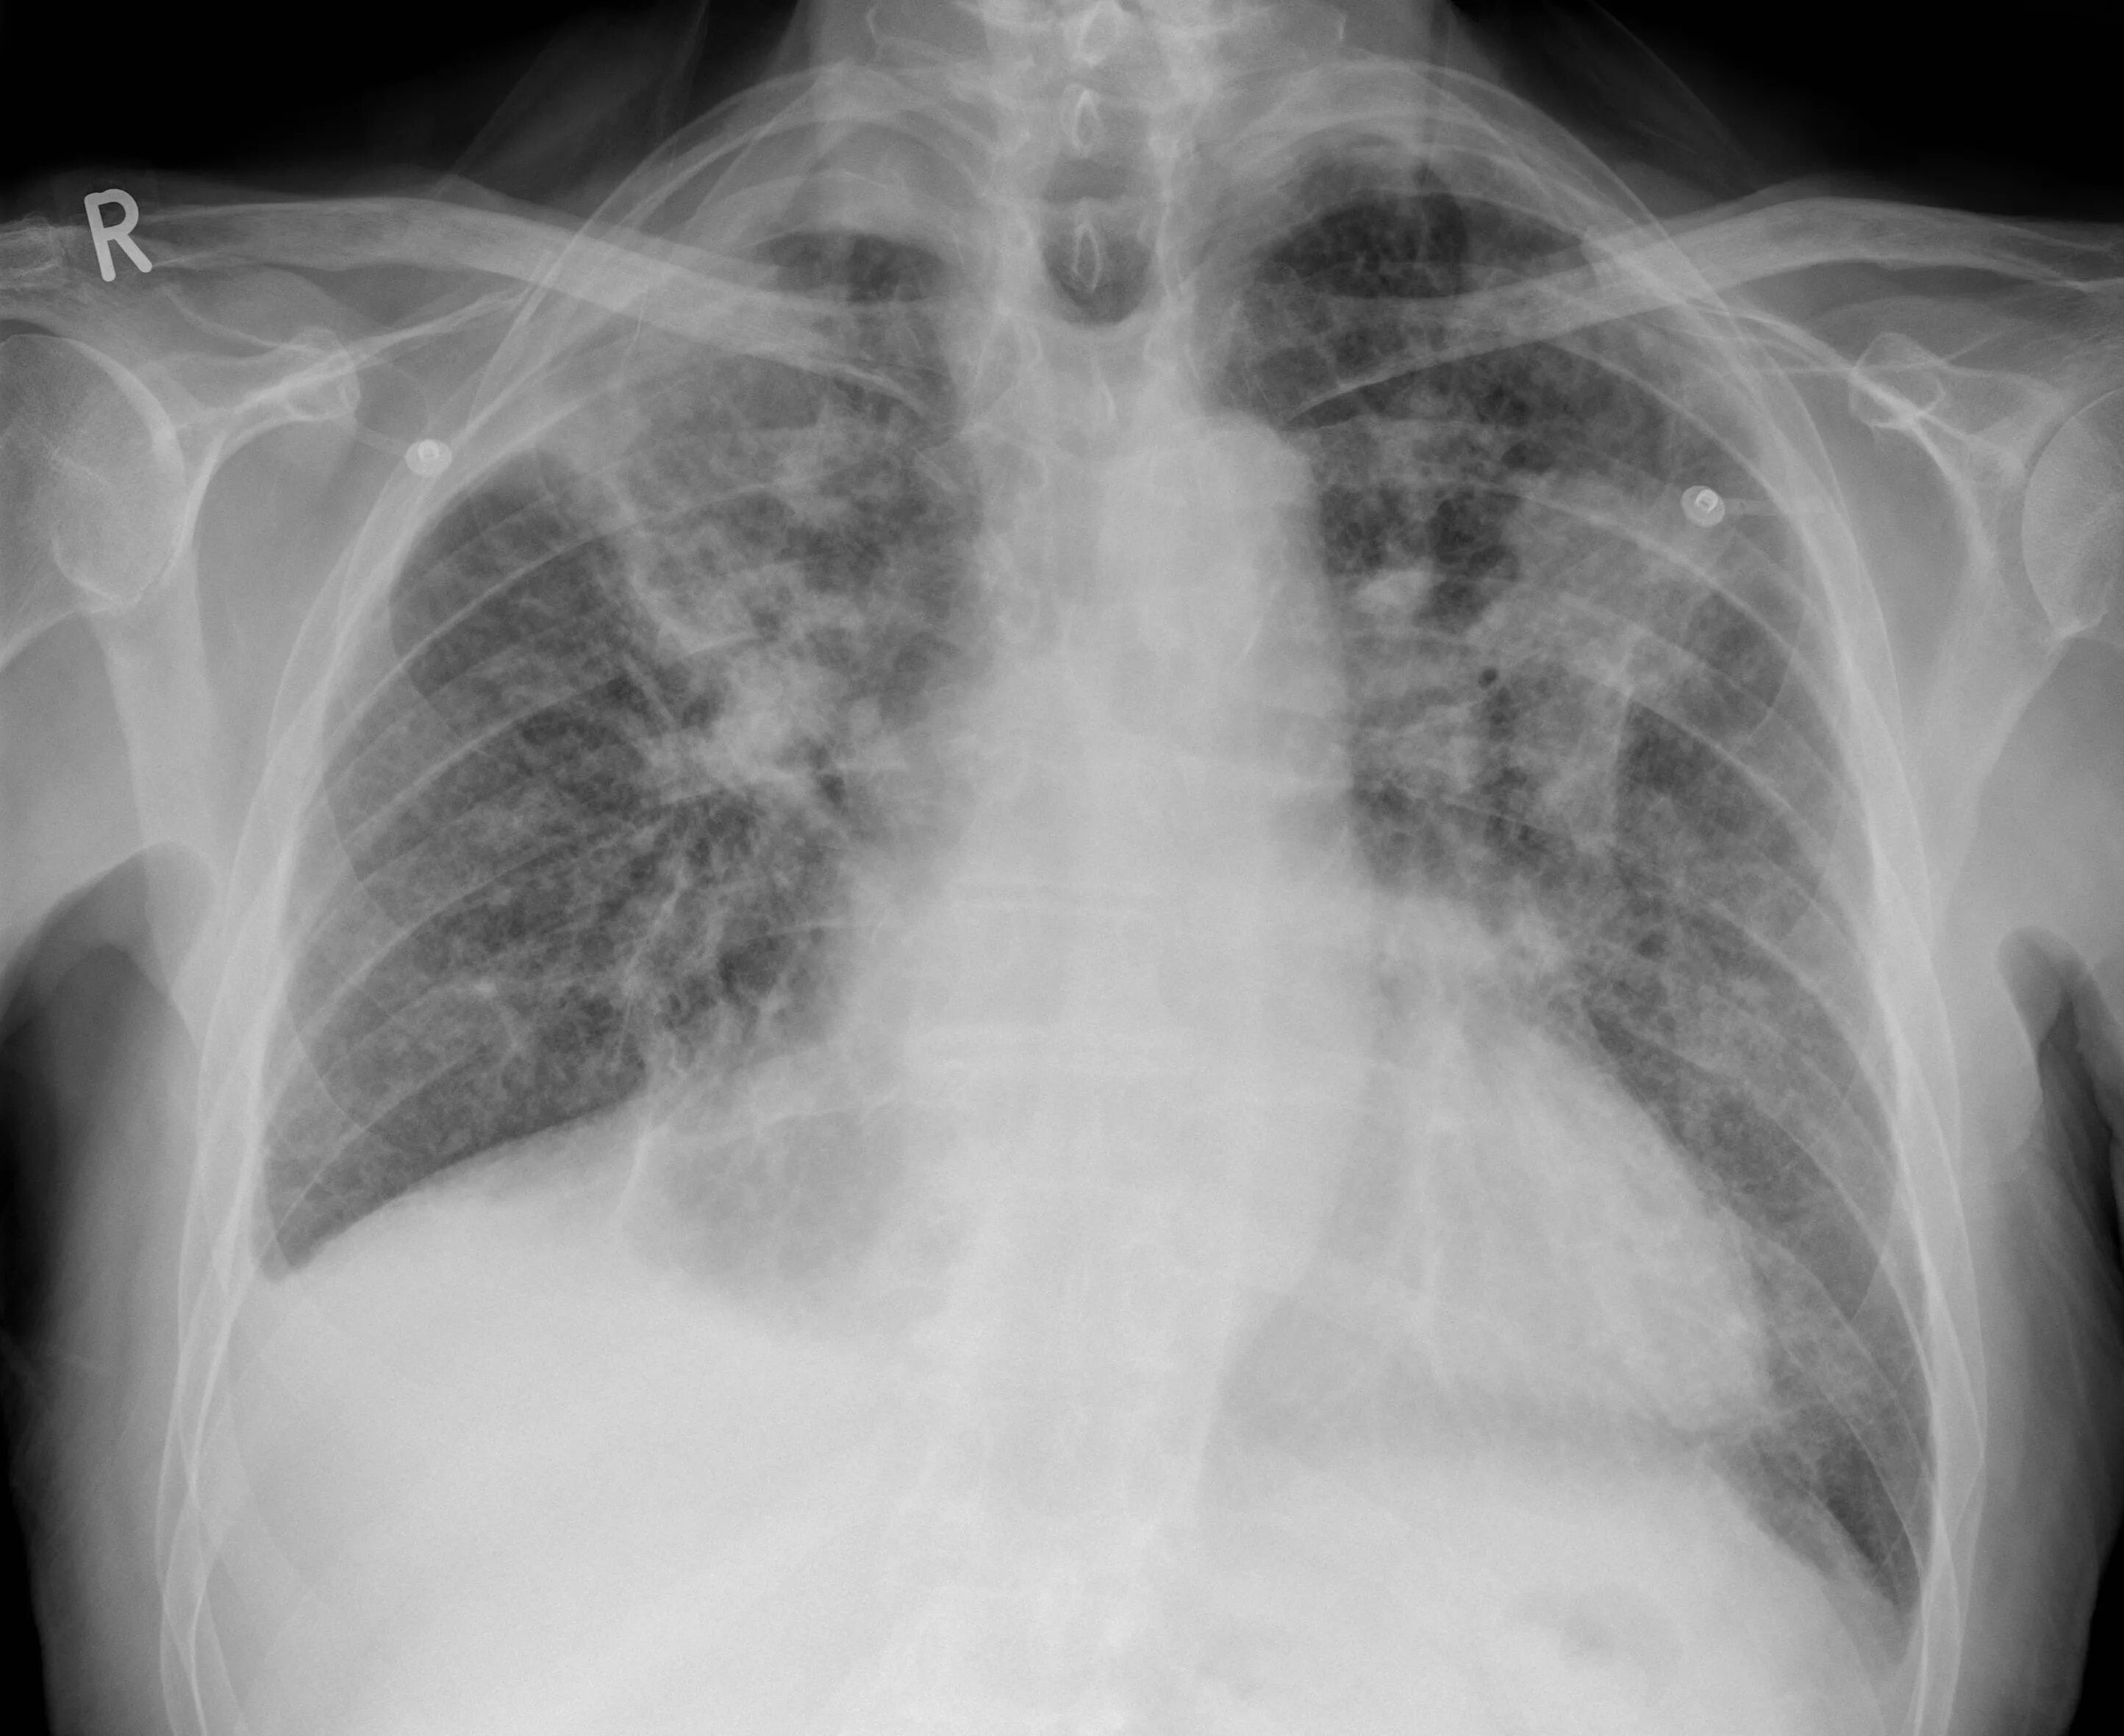

Как выглядит фиброз легких